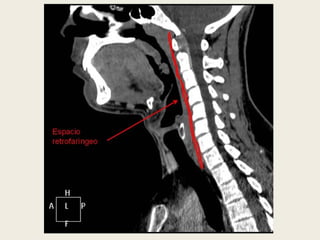

ESPACIO RETROFARÍNGEO

 Se sitúa en la línea media posterior, delimitado

por delante por la capa media de la fascia

cervical profunda, y por detrás y a los lados por la

capa profunda de la fascia cervical profunda.

 Se extiende desde la base del cráneo hasta el

cuerpo de D3.